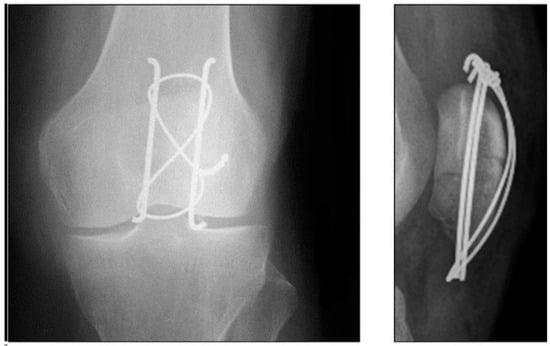

2.3. Tension Band Wire

- Benjamin, J.; Bried, J.; Dohm, M.; McMurtry, M. Biomechanical evaluation of various forms of fixation of transverse patellar fractures. J. Orthop. Trauma 1987, 1, 219–222. [Google Scholar] [CrossRef] [PubMed]

- Berg, E.E. Open reduction internal fixation of displaced transverse patella fractures with figure-eight wiring through parallel cannulated compression screws. J. Orthop. Trauma 1997, 11, 573–576. [Google Scholar] [CrossRef] [PubMed]

- Burvant, J.G.; Thomas, K.A.; Alexander, R.; Harris, M.B. Evaluation of methods of internal fixation of transverse patella fractures: A biomechanical study. J. Orthop. Trauma 1994, 8, 147–153. [Google Scholar] [CrossRef] [PubMed]

- Lotke, P.A.; Ecker, M.L. Transverse fractures of the patella. Clin. Orthop. Relat. Res. 1981, 158, 180–184. [Google Scholar] [CrossRef]

- Weber, M.J.; Janecki, C.J.; McLeod, P.; Nelson, C.L.; Thompson, J.A. Efficacy of various forms of fixation of transverse fractures of the patella. J. Bone Jt. Surg. Am. 1980, 62, 215–220. [Google Scholar] [CrossRef]